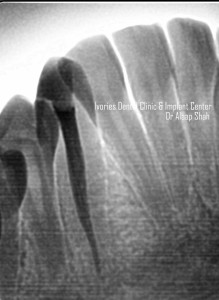

- 3D overview of anatomy of pulp canals

- Role of a pre-operative radiograph

- CASE DISCUSSION & ESTABLISHING DIAGNOSIS WITH RADIOGRAPHS